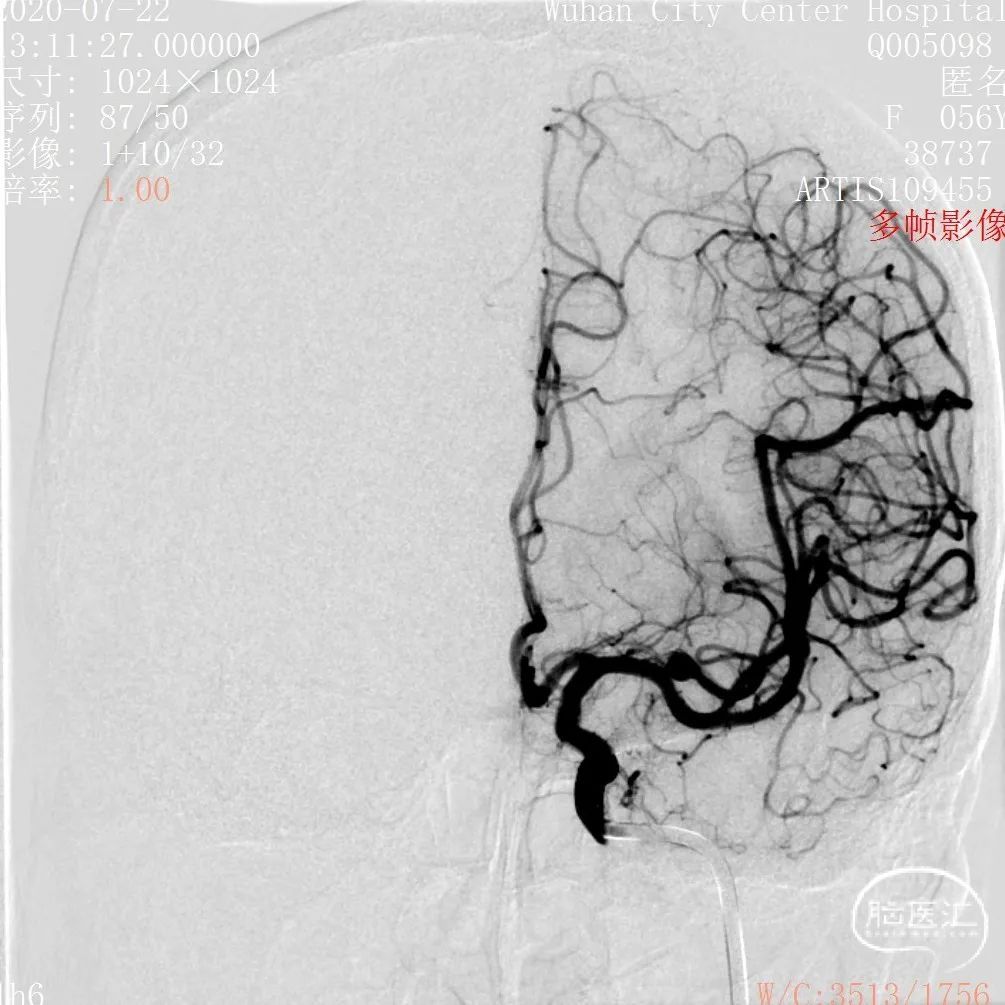

术前影像

DSA 2020-07-22

3D和测量